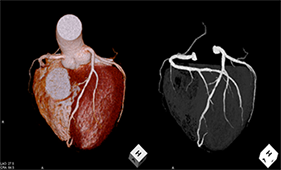

大動脈ステントグラフト

治療前   治療後

下肢動脈血管形成術

従来、放射線診断に用いられていた血管造影はCTやMRIの発展にともない、現在では主として治療目的のために行われています。この手法はIVR(インターベンショナル・ラジオロジー)と呼ばれています。

当院の血管造影室には、全身用にAlluraXperFD20、心臓血管造影用にはAlluraXperFD10/10(いずれもフィリップス社製)が導入され、フルデジタル化により再現性の高いデータを迅速に参照できるようになり、より精度の高い検査と治療を行っています。